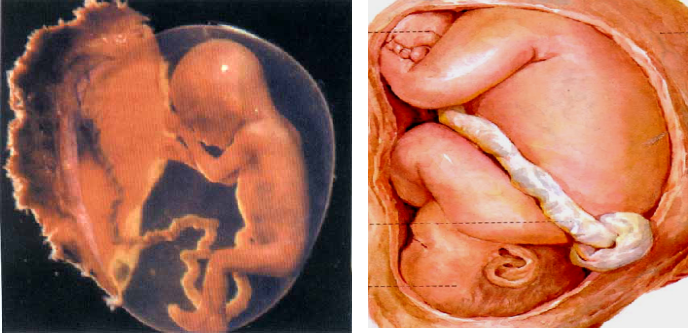

人胚胎在母体子宫中的发育经历38 周(约266 天),可分为三个时期:

①胚前期(preembryonic period): 受精-第2周末二胚层胚盘出现。

②胚期(embryonic period):第3周至第8周末胚的各器官、系统与外形发育为初具雏形的胎儿(fetus)。此时只有3 厘米长,堪称“袖珍人”。

③胎期(fetal period):第9周-出生,胎儿逐渐长大,各器管、系统继续发育,多数器官出现不同程度的功能活动。

胚期质变剧烈,胎期量变显著。因此,胚期是研究和学习的重点